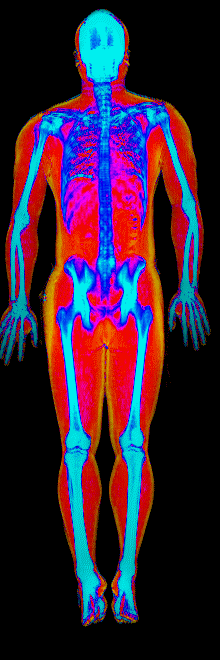

What Fat Loss Looks Like on a DEXA Scan

Lost 30.2 lb of fat, gained 3.9 lb lean · 240 → 214 lb · Age 43

Lost 27.9 lb of fat · 225 → 191 lb · Age 40

Lost 23.7 lb of fat · 186 → 155 lb · Age 34